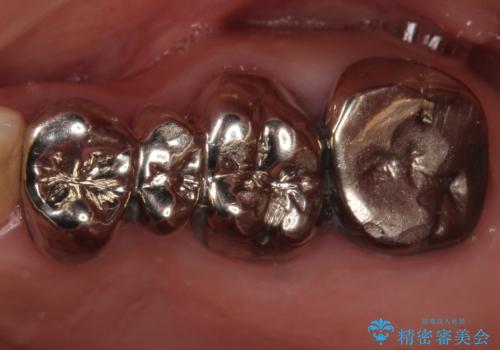

- 左下6 セラミックインレー 77,000円×1本費用は治療当時の料金となります

継ぎ接ぎになった樹脂の詰め物から一塊のセラミックインレーに置き換えることで着色や二次う蝕のリスクを抑えます。